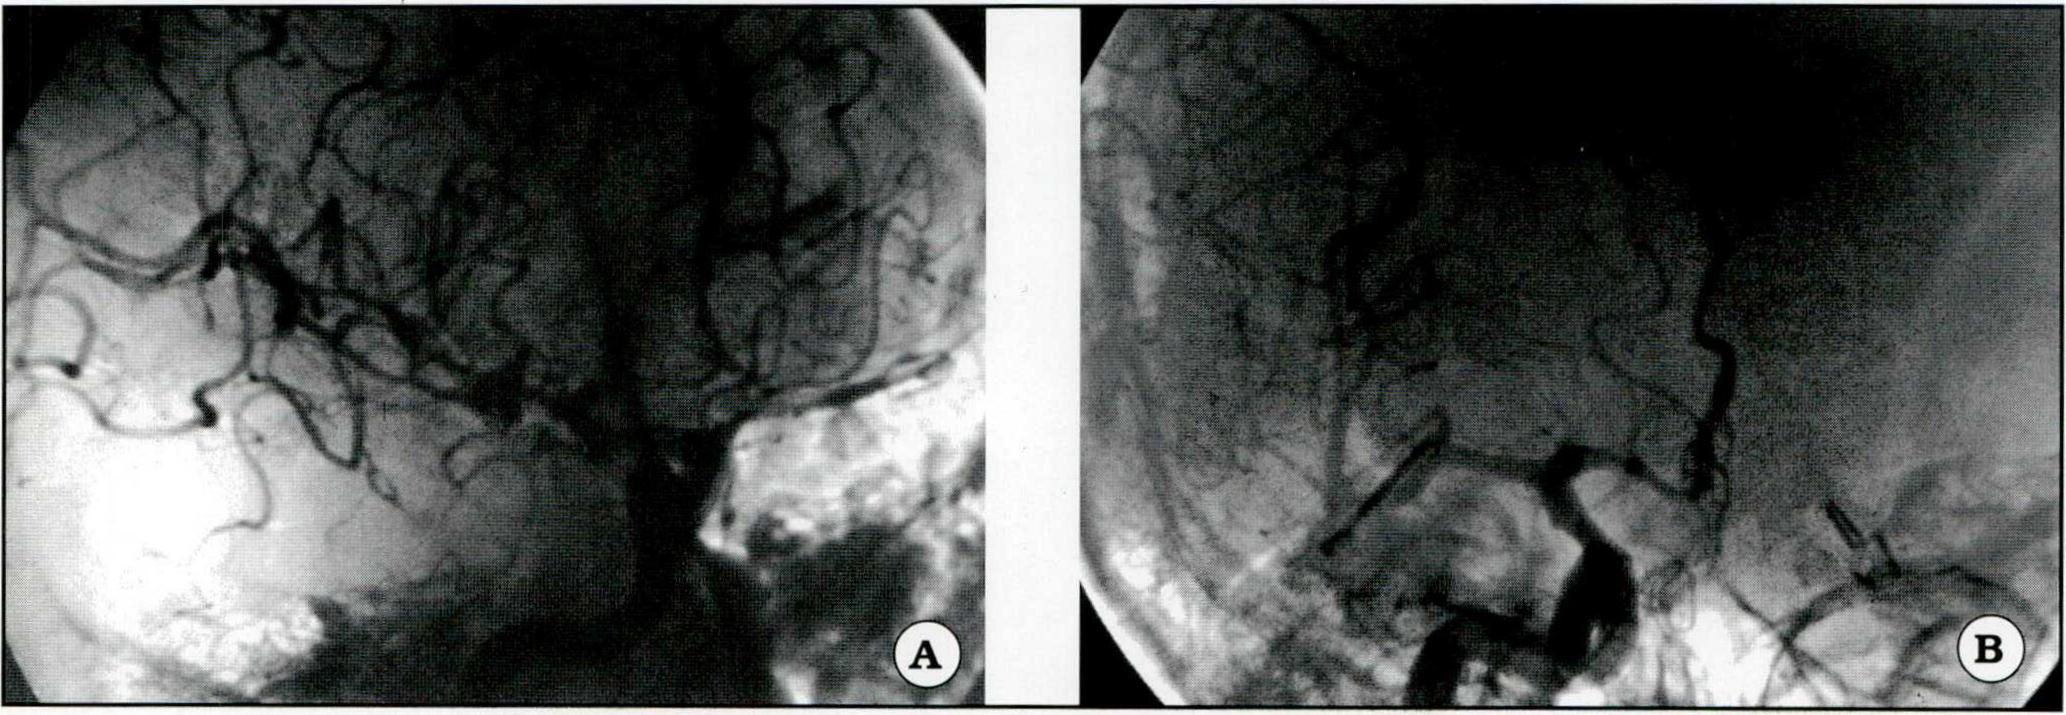

Fig 2. A. Angiografía en posición frontal de un aneurisma carotídeo. B. Se visualiza el clipado del aneurisma con importante vasoespamoo.

Fig. 3. A. Aneurismas múltiples. Se observa el aneurisma silviano derecho y un clip aplicado a un aneurisma carotídeo izquierdo. B. Clipado del aneurisma silviano.